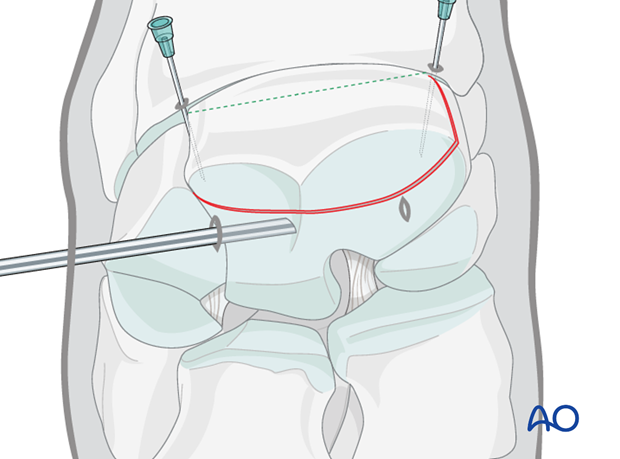

The proximal medial and lateral margins of the fracture are defined by arthroscopically guided percutaneous insertion of 18 gauge hypodermic needles.

It is important that these needles are placed perpendicular to the dorsal surface of the carpus in order to accurately delineate the fracture width.

Two 18 gauge spinal needles are then placed over the central portion of the radial and intermediate facets of the third carpal bone. These two needles are close and parallel to the proximal articular surface and directed approximately perpendicular to the fracture line. These needles are critical guides for implant placement. Once the spinal needles have been placed, the lateral and medial hypodermic needles are removed.

A further 18 gauge needle is inserted into the carpometacarpal joint.